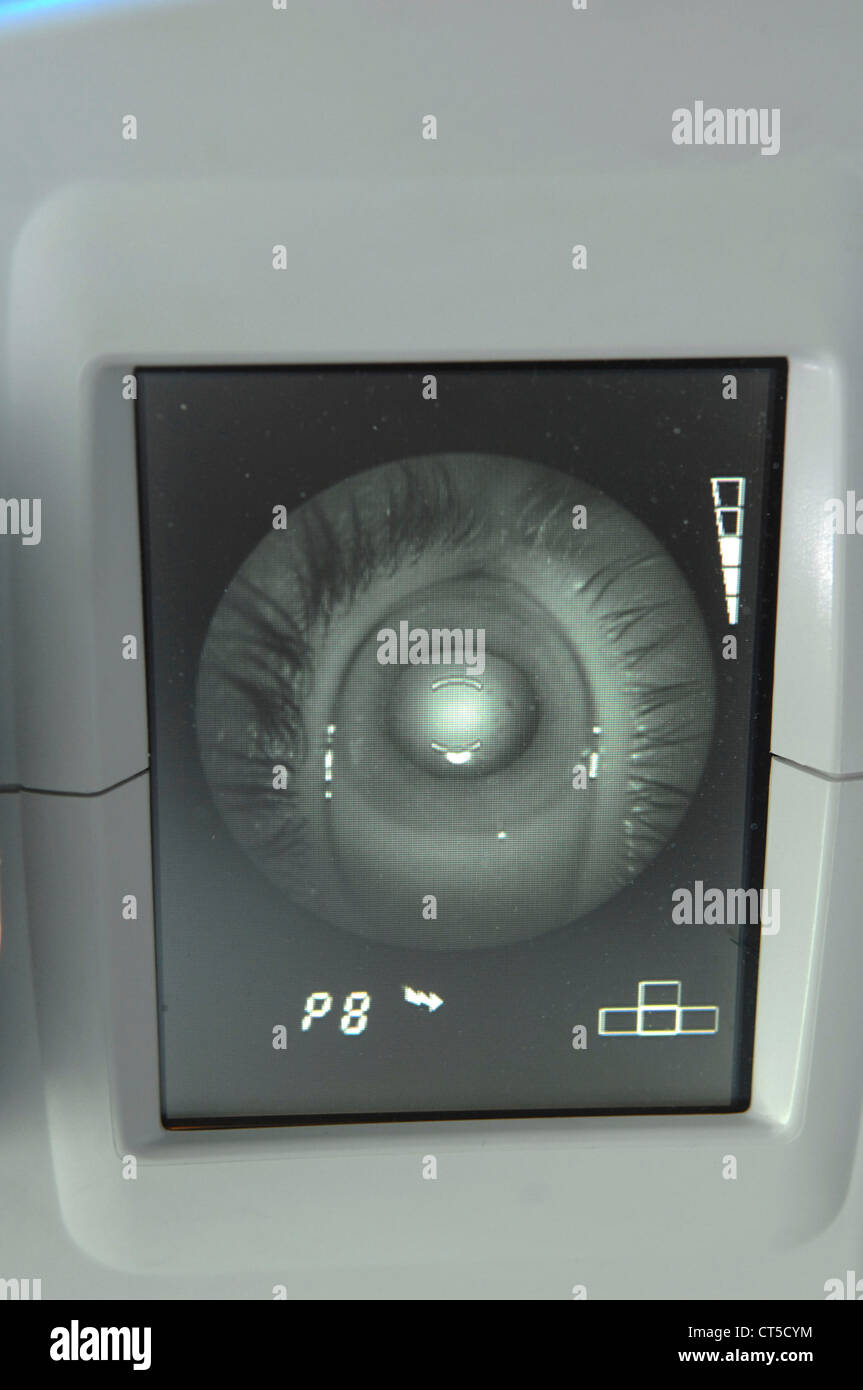

FUNDUS OCULI EXAMINATION Stock Photohttps://www.alamy.com/image-license-details/?v=1https://www.alamy.com/stock-photo-fundus-oculi-examination-49292424.html

FUNDUS OCULI EXAMINATION Stock Photohttps://www.alamy.com/image-license-details/?v=1https://www.alamy.com/stock-photo-fundus-oculi-examination-49292424.htmlRMCT5CYM–FUNDUS OCULI EXAMINATION